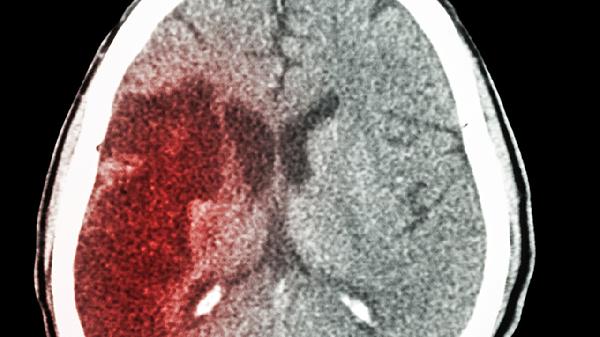

腦出血恢復(fù)期發(fā)燒是怎么回事?

腦出血恢復(fù)期發(fā)燒可能與感染、中樞性發(fā)熱、藥物反應(yīng)、深靜脈血栓形成或吸收熱等因素有關(guān)。腦出血患者可通過抗感染治療、物理降溫、調(diào)整用藥、預(yù)防血栓形成或?qū)ΠY處理等方式緩解癥狀。